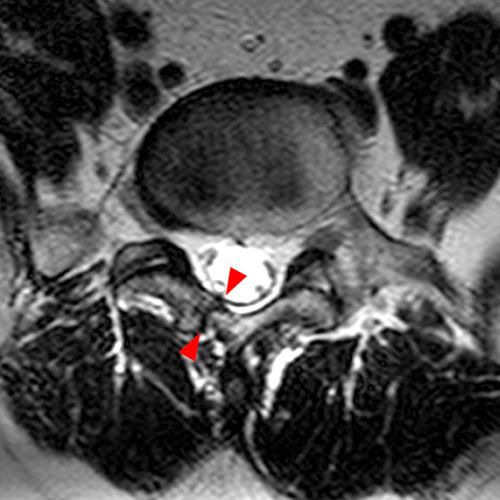

Case 2: T1-weighted (4A) and T2-weighted (4B) axial images show T1 hypointensity and T2 hyperintensity (arrowheads) in the left lamina of L5 adjacent to a small hypointense line (arrows) which traverses the lamina.

Case 2: Acute left-sided laminolysis